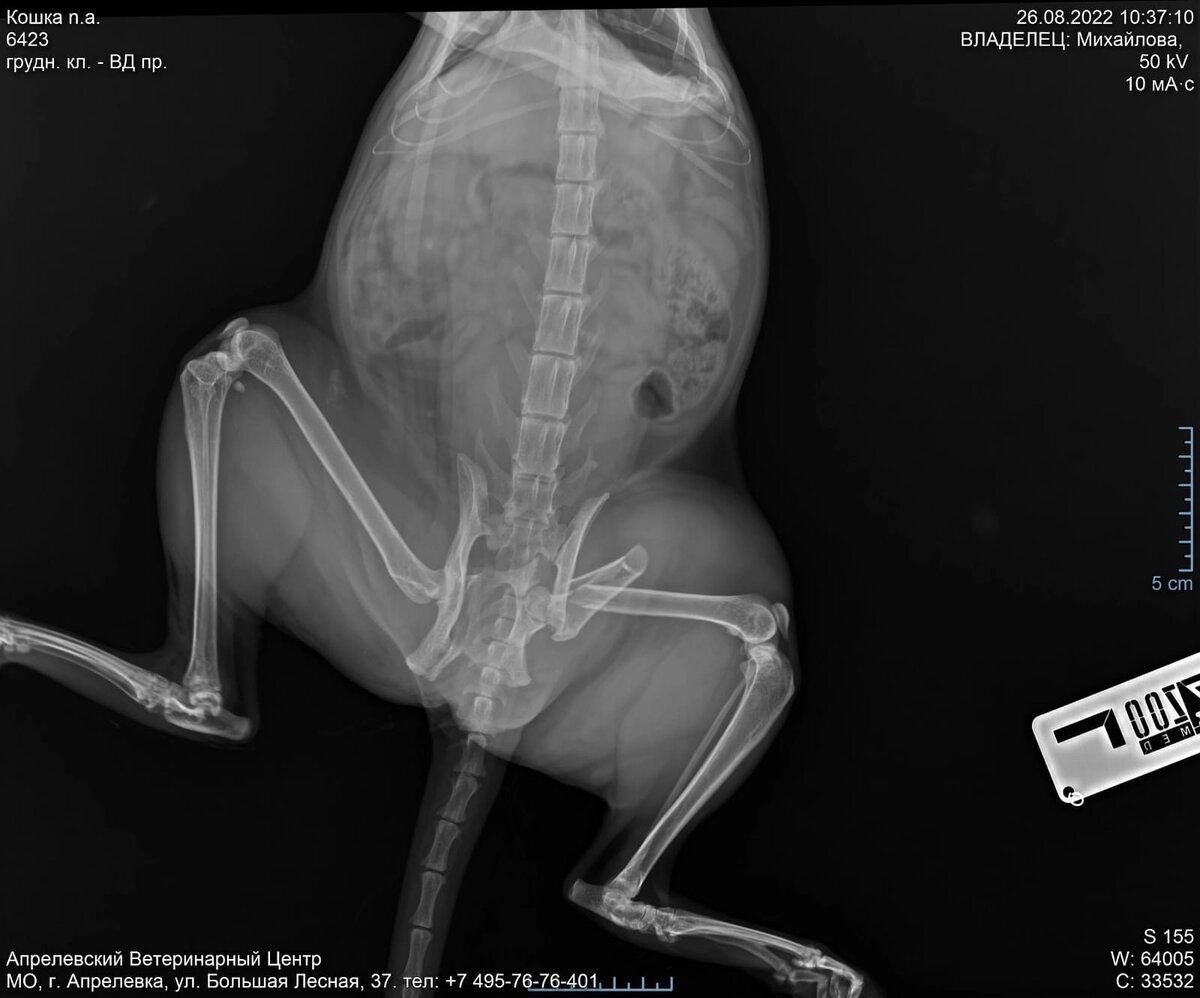

Ее дом находится на углу улицы, и с двух сторон окружен дорогой,и на этой дороге она нашла нашу Малыху. Она поместила ее в коробку на теплой террасе, предварительно сделав рентген, по которому было понятно-что ее скорее всего сбило машиной..

Вот с этой фотографии все началось.

Немного выдохнув я написала знакомому вет врачу-Маше, которая помогала мне с прививками иногда, скинула ренген, и результат меня ошарашил..Маша сказала, что там не только перелом лапы, а под вопросом перелом тазовой кости и еще скакалка...и что операция будет стоить очень дорого...

вот такой был первоначальный ренген